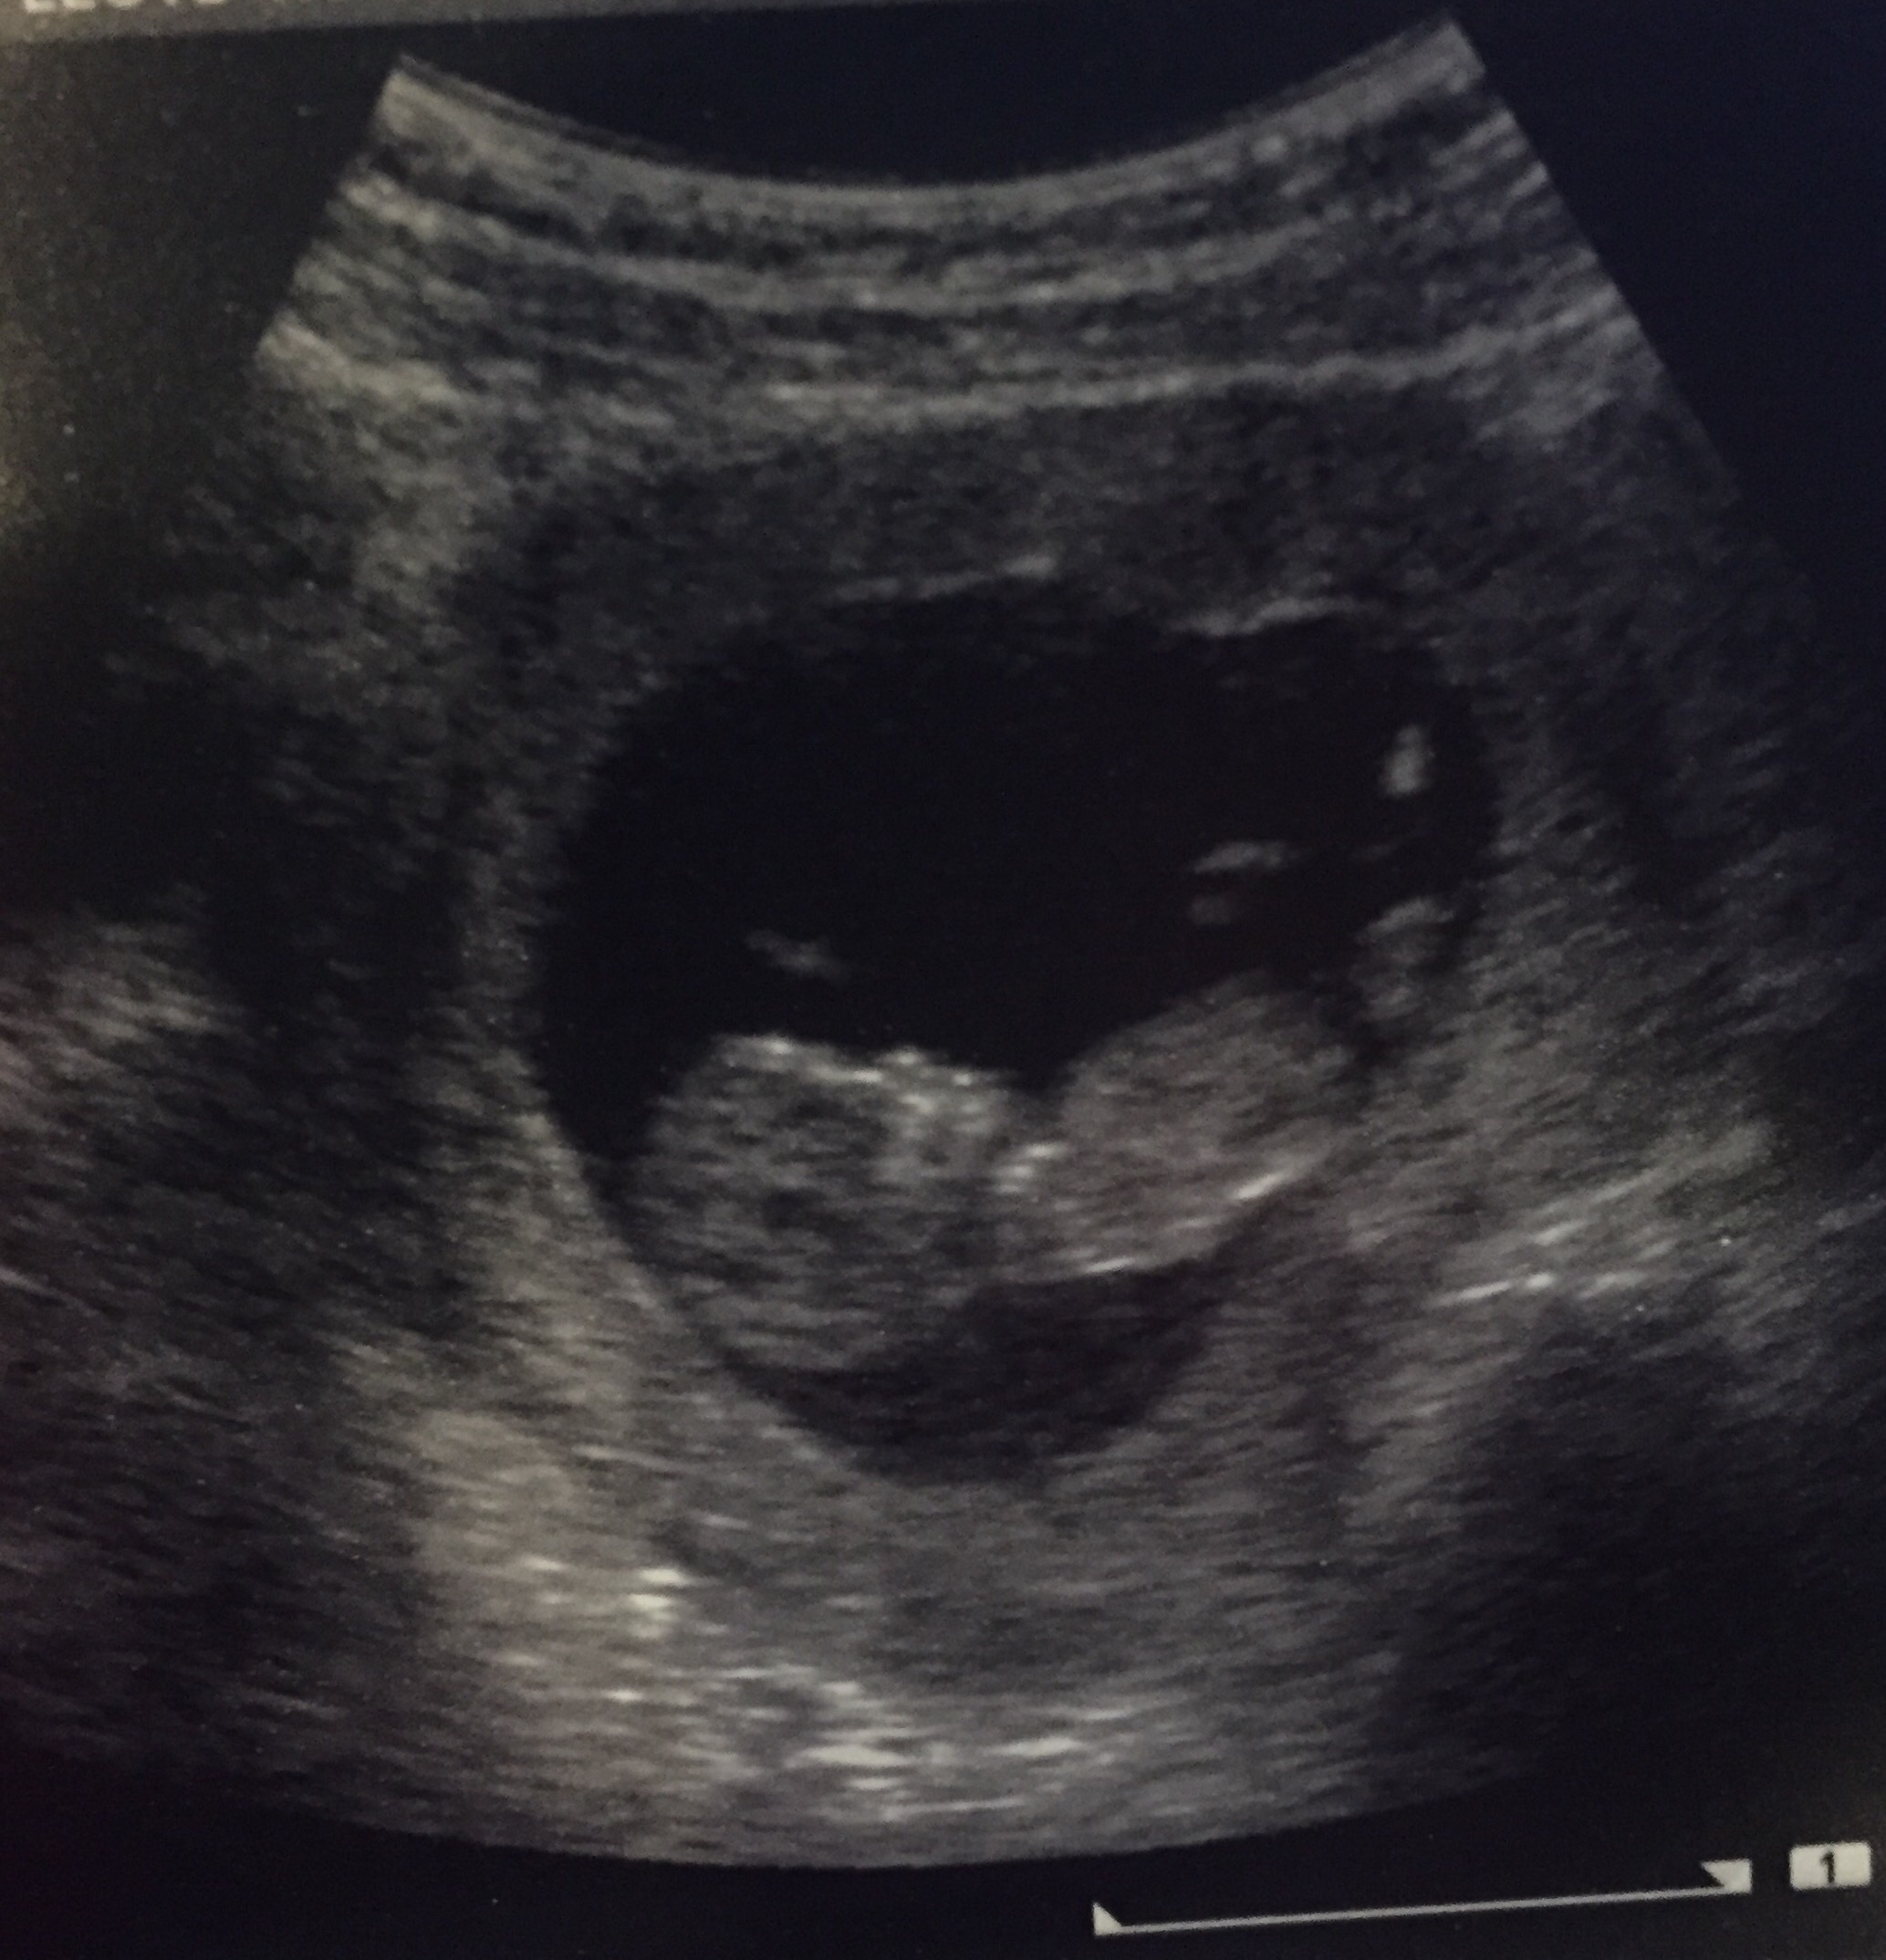

We got the ultrasound on Monday, when I was 9 weeks 3 days. Our doctor told me that I'm measuring slightly bigger, maybe 10 weeks, but it's too early to tell. Lots of wiggling happening and everything looks healthy so far!

We go back on October 5th for the next ultrasound (I'll be roughly 11.5 weeks).